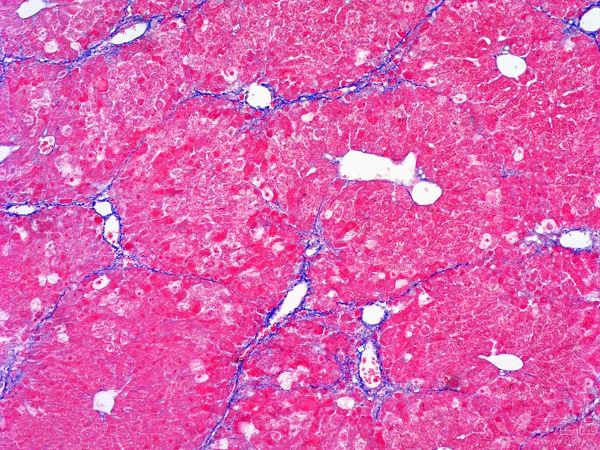

①正常組織染色結果

在正常組織中,MASSON染色通常呈現出均勻的藍色背景,其中肌肉纖維和血管等結構清晰可見。這種染色結果表明組織結構正常,無明顯的纖維化病變。